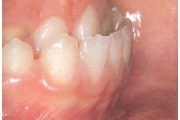

Suulaepoolt lõikunud koonilise kujuga lisahammas